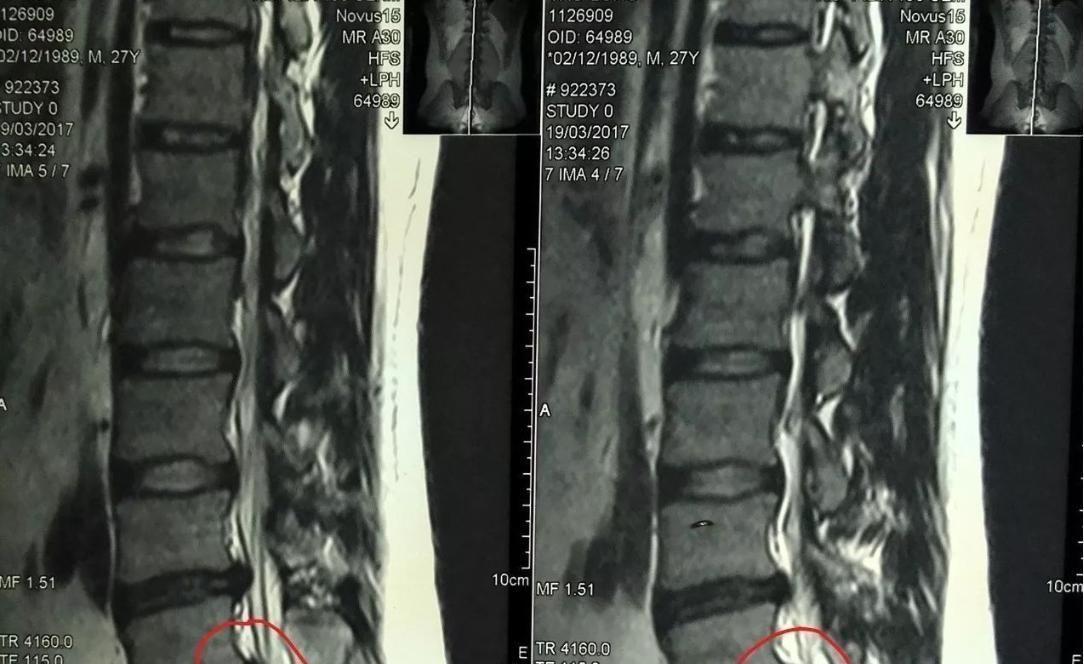

李先生,2012年2月因为劳累又出现左侧臀部疼痛又来找韩及林诊治。患者来前,曾经痛苦难耐,到当地医院诊治,核磁检查:1.腰4/5椎间盘左后突出;2.腰椎退行性变。(见下图),医院建议手术治疗。因不愿第二次手术,再次来所寻求保守治疗。

【 手术治疗|腰椎间盘突出真实经历过程,腰椎间盘突出症原来可以这么做】当时该患者左侧臀部疼痛,牵涉到大腿后面,小腿外侧,疼痛剧烈,性质为火辣辣的痛,翻身加重,左侧小腿到脚发麻,站立和走路时加重,大小便正常,不能直腰,走路跛行,候诊时坐卧不安。

患肌检查:评估臀中肌,臀大肌,股二头肌,腓肠肌,腓骨长肌为患肌。

经过浮针扫散配合加中药酒,三个疗程,临床症状消失。

4.近期的腰椎核磁结果相当严重,症状也非常严重,浮针治疗依然效果不错。